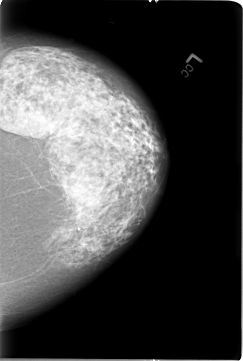

B_3026_1.RIGHT_MLO

B_3026_1.LEFT_MLO

B_3026_1.RIGHT_CC

B_3026_1.LEFT_CC

PATIENT_AGE 75

DENSITY 3

LESION_TYPE MASS SHAPE IRREGULAR-ARCHITECTURAL_DISTORTION MARGINS OBSCURED-ILL_DEFINED-SPICULATED

ASSESSMENT 4

SUBTLETY 3

PATHOLOGY MALIGNANT

LESION_TYPE CALCIFICATION TYPE PLEOMORPHIC DISTRIBUTION CLUSTERED